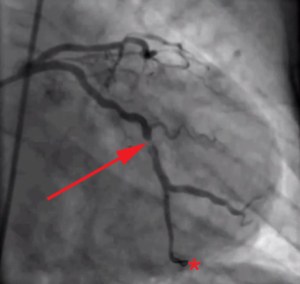

Coronary_angiography_of_a_STEMI_patient,_showing_partial_occlusion_of_left_circumflex_coronary_artery

Based on the GXT results a cardiologist may recommend an angiogram, in which a catheter is inserted into an artery and threaded into the coronary arteries, dye is injected, and the coronary arteries are viewed through X-ray imaging. This allows cardiologists to actually see the extent of the narrowing in the coronary arteries.